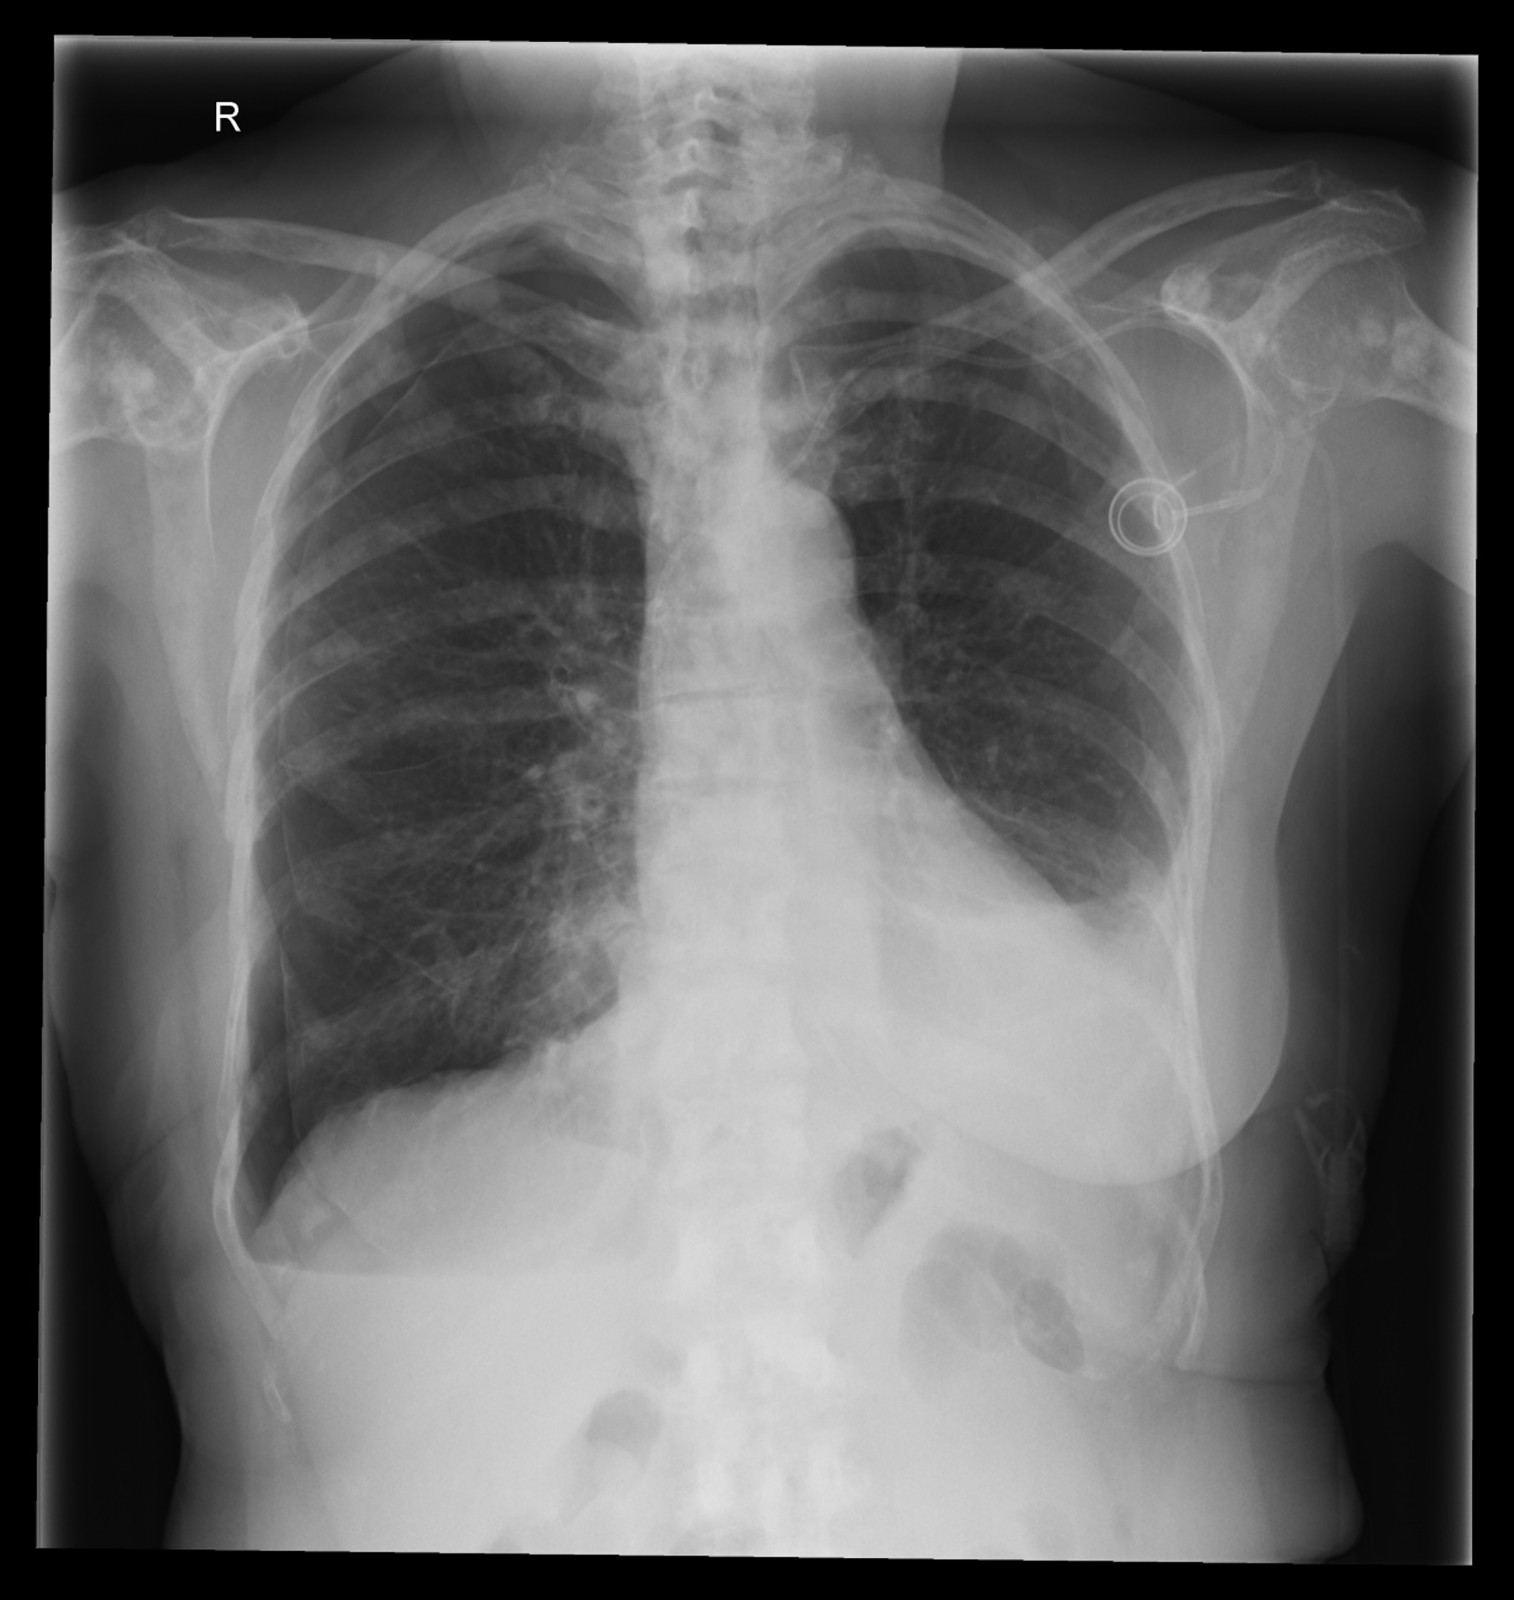

Röntgenfall des Monats Mai 2017 mit Auflösung

74 jährige Patientin mit diffusen Skelettschmerzen und akut aufgetretener Dyspnoe. Z.n. Mammakarzinom rechts.

ap

Bild vergrössern